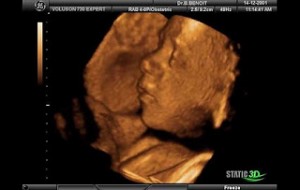

Hamileliğin (Gebeliğin) 35. Haftası Resim ve Video;

Bebeğin Boyutu: 43.7 cm, 1.9 kg

Çocuğun gelişimi: akciğerler alveollerin genişlenmesini sağlayacak ve doğduktan sonra bebeğinizin nefes alması için önemli olan surfaktan (Surfaktan maddeler en basit tanımı ile bir sıvının yüzey gerilimini azaltan maddelerdir) üretiyor.

Böbrekler tamamen gelişmiştir.

Bu haftadan itibaren artık bebek rahim içerisinde oldukça fazla yer kaplar ve bu yüzden ona hareket edecek fazla alan kalmaz. Eğer bebeğinizin hareketlerinde azalma his ederseniz endişe etmeyin, hareketlerin azalması bu yüzdendir.